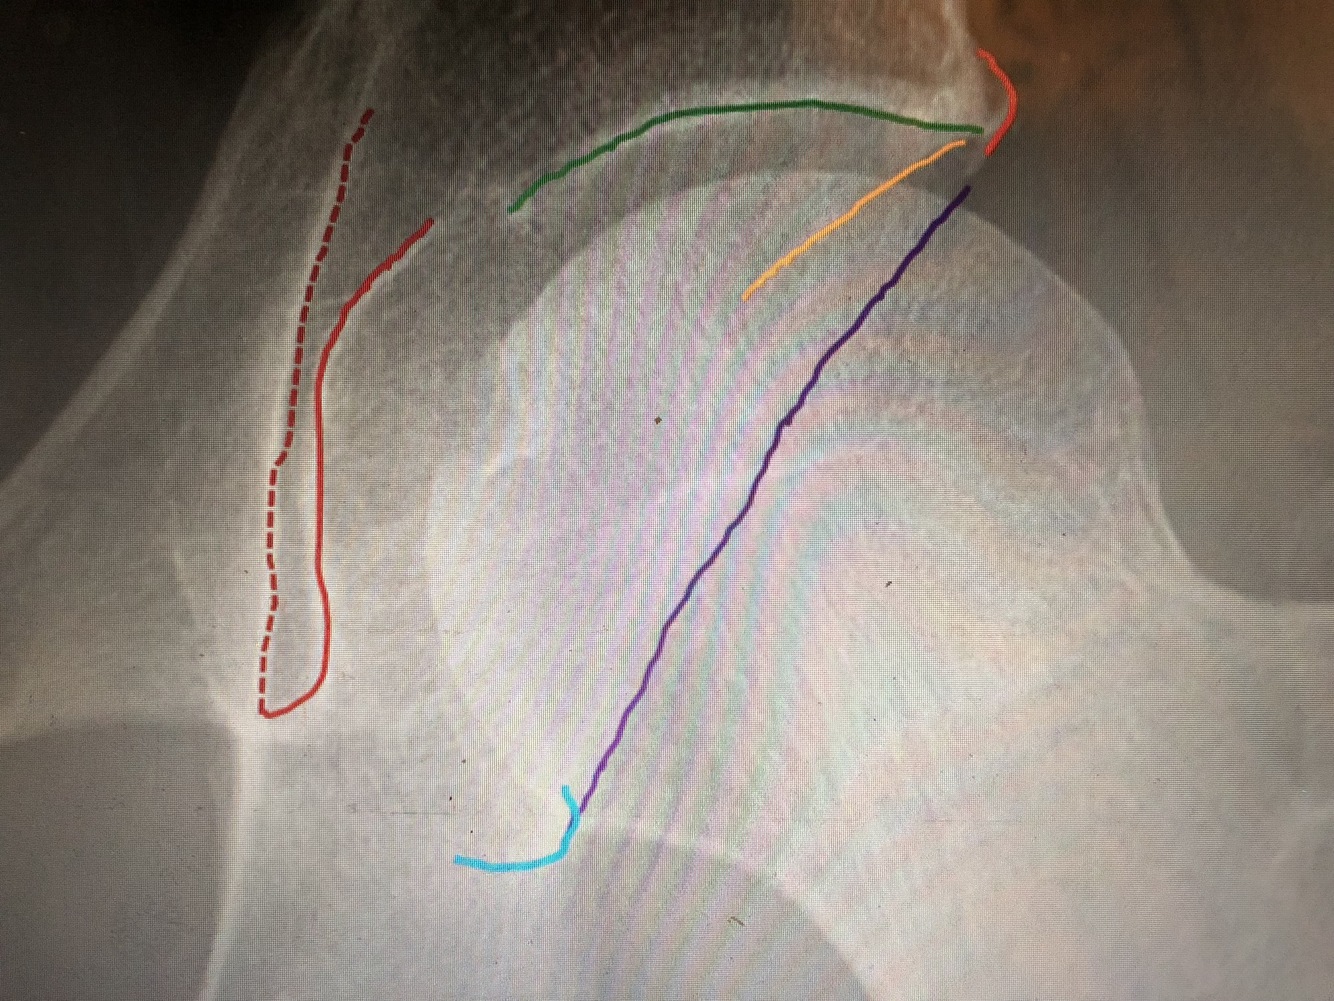

What is the green line?

Medial margin of femoral neck

What is the purple line?

Lateral margin of femoral neck

What is the red line?

Lesser trochanter

What is the blue line?

Greater trochanter

What is the yellow line?

Floor of trochanteric fossa (looks like part of intertrochanteric crest, but is not)